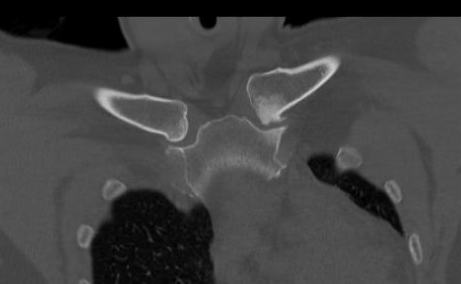

CT scan

Left posterior SCJ dislocation with pre- and post angiogram

Severe left posterior SCJ dislocation with subclavian vein compression